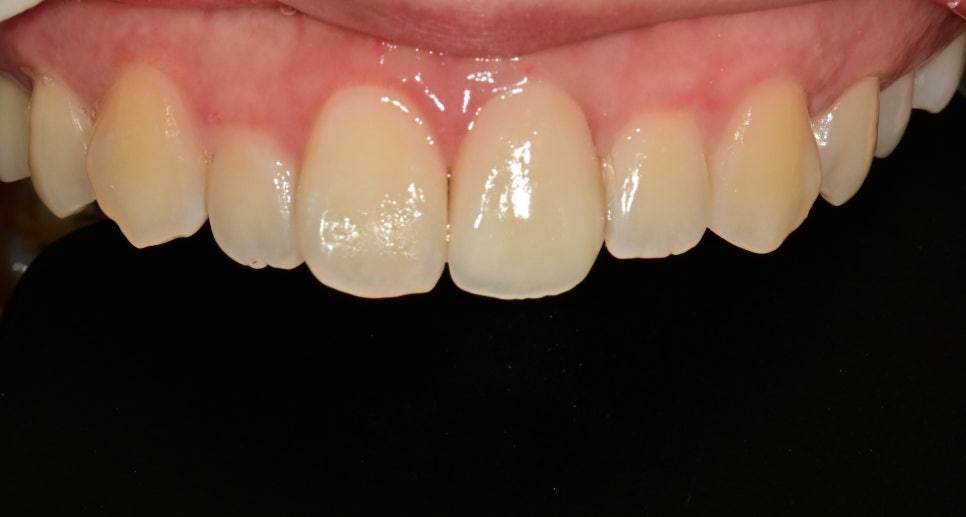

최종 크라운 치료 후 사진입니다

주변 잇몸의 외상도 깨끗하게 회복이 되었고

바로 옆 치아와 형태, 색상에 있어서 이질감 없이 자연스러운 보철물이 제작되었습니다.

해당 케이스와 같은 경우는

다행히 신경이 안정이 되어 신경치료 없이 치료가 완료될 수 있었지만

파절의 범위가 커서 레진 치료보다는 크라운치료가 적절한 대안이 될 수 있었습니다.